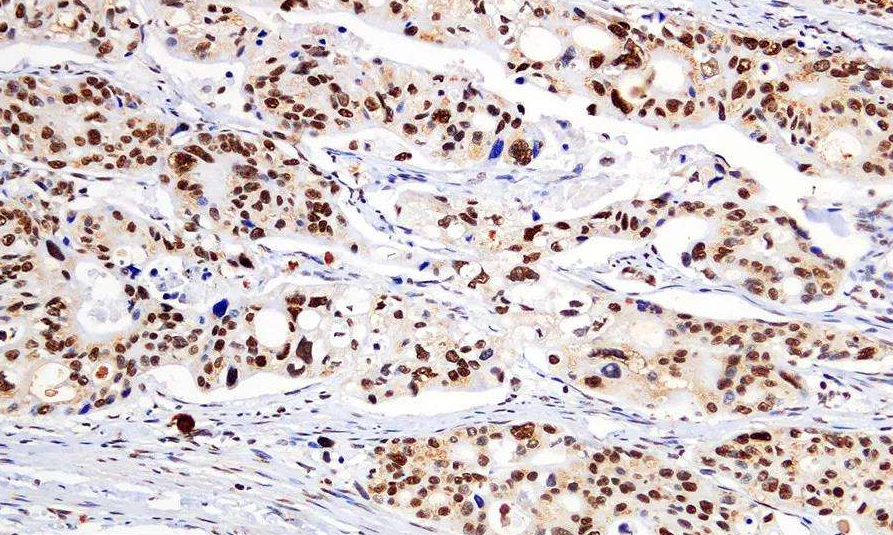

IHC技术现在是很成熟的方法,但是对IHC照片的分析并没有一个威势的说法,镜下观察免IHC的样品,细胞核被染上蓝色,胞浆间有(强阳性的地方会呈现棕黄色)用肉眼观察IHC切片的结果只能是定性的,不准确的,使用灰度值定量或半定量对照片测量出一个数值,在准确性和说服力上比起肉眼观察主观判断有了明显的提升。